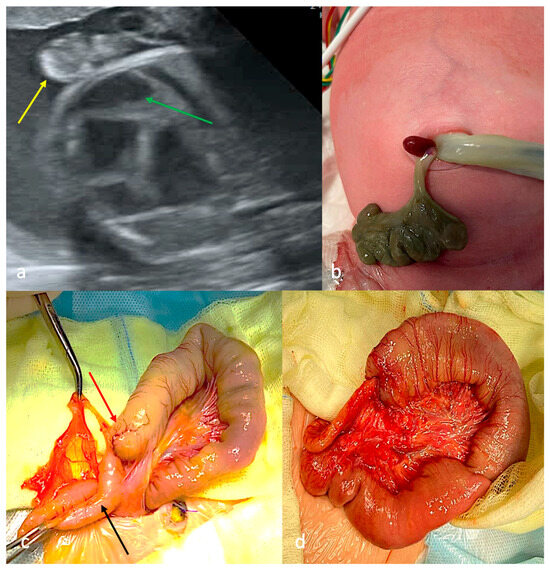

Closing/Closed Gastroschisis (CGS): Antenatal Predictors and Surgical Strategies in Cases of Unique Anatomy from a Case Series

Background: Closing/closed gastroschisis (CGS) accounts for approximately 6% of gastroschisis cases globally. Currently, no consensus exists regarding: antenatal predictors of CGS types, optimal antenatal management (ultrasound screening frequency, indications for early delivery), or standardized surgical strategies tailored to CGS type (staging/timing of [...] Read more.

Background: Closing/closed gastroschisis (CGS) accounts for approximately 6% of gastroschisis cases globally. Currently, no consensus exists regarding: antenatal predictors of CGS types, optimal antenatal management (ultrasound screening frequency, indications for early delivery), or standardized surgical strategies tailored to CGS type (staging/timing of procedures, enterostomy necessity/level). Methods: Five neonates with CGS were enrolled and classified according to Perrone’s classification: two patients with type B (40%), one with type C (20%), one with type D (20%), one patient was classified as unclear (20%). Gender distribution—80% female (n = 4), 20% male (n = 1); gestational age—median 35 weeks (IQR 35–38); preterm birth rate—80% (n = 4); birth weight—median 2620 g (IQR 2310–3850). Results: Three patients (60%) developed antenatal intestinal obstruction signs at the third trimester, including two who postnatally demonstrated viable intestinal loops. Two patients (40%) with necrosis of eviscerated intestine demonstrated onset of antenatal intestinal obstruction signs at the second trimester. Patients with CGS type B were managed using a staged surgical approach; patients with types C and D received single-stage repair. Patient with CGS type B achieved complete clinical recovery. Three patients (60%) with CGS types C and D developed short bowel syndrome. Conclusions: The appearance of sonographic signs of intestinal obstruction in the second trimester may be a predictor for a high risk of subsequent significant vascular compromise of the eviscerated bowel, leading to more severe types of CGS (C and D). For patients with CGS type B, a staged surgical approach is advisable to maximize bowel length preservation. Full article

Show Figures

Figure 1